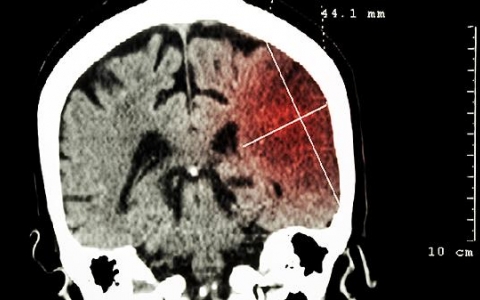

颅内血肿是指患者大脑受到创伤,造成脑内出现血管破裂从而引起的血肿,根据疾病发生的部位不同,所出现的血肿类型也会不同,患者会出现很明显的症状,会危害患者的身体健康